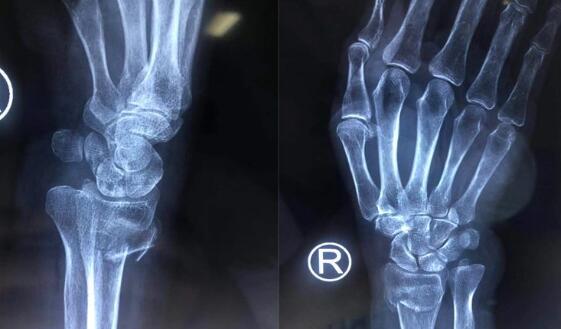

经过检查发现,老太太的右桡骨远端粉碎性骨折,骨折移位严重。手外二病区的熊祖国医师告诉王老太的家属,高龄老年患者骨质疏松,骨折愈合缓慢,选择夹板固定的保守治疗非常容易导致骨折再次移位;同时夹板固定时间长,严重影响右手、右腕功能,导致关节僵硬、活动受限,还可能会引起一些并发症,降低生活的质量。而且王老太骨折断端错位比较严重,石膏外固定已无法恢复。王老太及家人同意手术治疗。

术中熊祖国医师用了微创手术,在其右腕内侧作了仅2厘米的切口,并用T形钢板内固定,手术很顺利,一小时完成。熊医师介绍,王老太手术后无需夹板等外固定,术后第二天就可以正常活动右手及右腕关节。